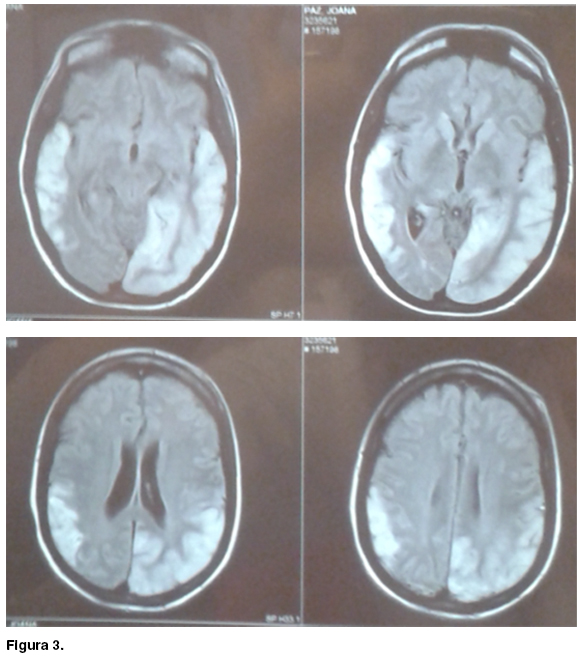

Las demás rutinas sanguíneas fueron normales y la serología para VIH fue no reactiva. La resonancia magnética (RM) encefálica muestra un área cortico-subcortical temporo-parietal derecha isointensa en T1, hiperintensa en T2 y FLAIR, con restricción en difusión, compatible con área de isquemia aguda del territorio superficial de la ACM derecha. Se destaca el signo del pulvinar bilateral. No hubo alteraciones en el sector venoso ni arterial (figura 2).

En sala de medicina agrega episodios de heteroagresividad y trastorno del campo visual compatible con hemianopsia homónima derecha. Con planteo de nuevo ACV se solicita nueva neuro-imagen que muestra un área cortico-subcortical a nivel temporo-parieto-occipital izquierdo, caracterizada por aumento de la señal en T2 y FLAIR con restricción en la difusión, compatible con nueva lesión isquémica que esta vez, no respeta territorio arterial alguno (figura 3).

Los eventos focales de tipo ACV debutan característicamente antes de los 15 años y usualmente antes de los 40 años (2). Como se aprecia en la neuroimagen de la paciente, los mismos no respetan territorios vasculares arteriales y predominan en la topografía parieto-occipital. (1,2) El hallazgo de calcificaciones gangliobasales también es característico, así como el signo del pulvinar bilateral, el cual además de la MELAS, también puede verse en la enfermedad de Fabry, el sindrome de Wernicke-Korsakoff y la enfermedad de Creutzfeldt-Jakob. (4)